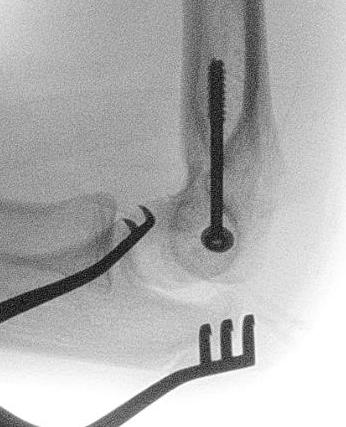

Incarcerated medial epicondyle fracture

![]()

Incarcerated medial epicondyle fragment

Etiology

Elbow dislocation which has self reduced / been reduced

Clinical / Xray

If patient < 5 years may not be ossified

- significant pain

- ulna nerve symptoms

- limited ROM

- absent medial epicondyle on xray / compare to contralateral side

- non congruent joint reduction

- consider CT / MRI / arthrogram / open exploration

Management

Youtube incarcerated medial epicondyle fixation video

Vumedi incarcerated medial epicondyle fixation video

Open reduction

- medial approach

- identify and protect ulna nerve

- retrieve medial epicondyle